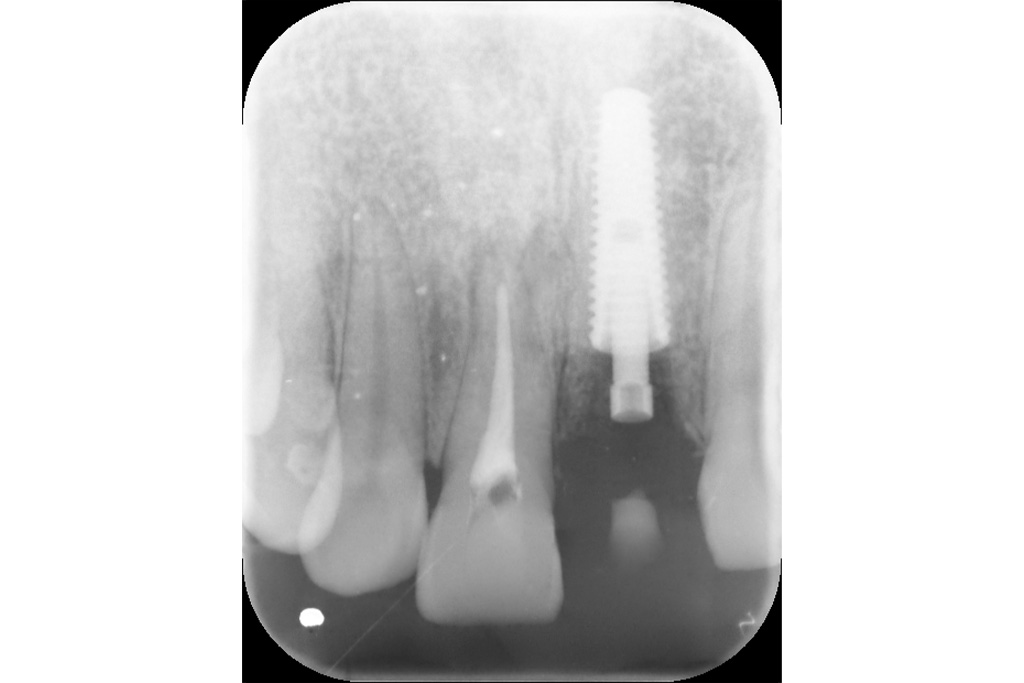

治療後